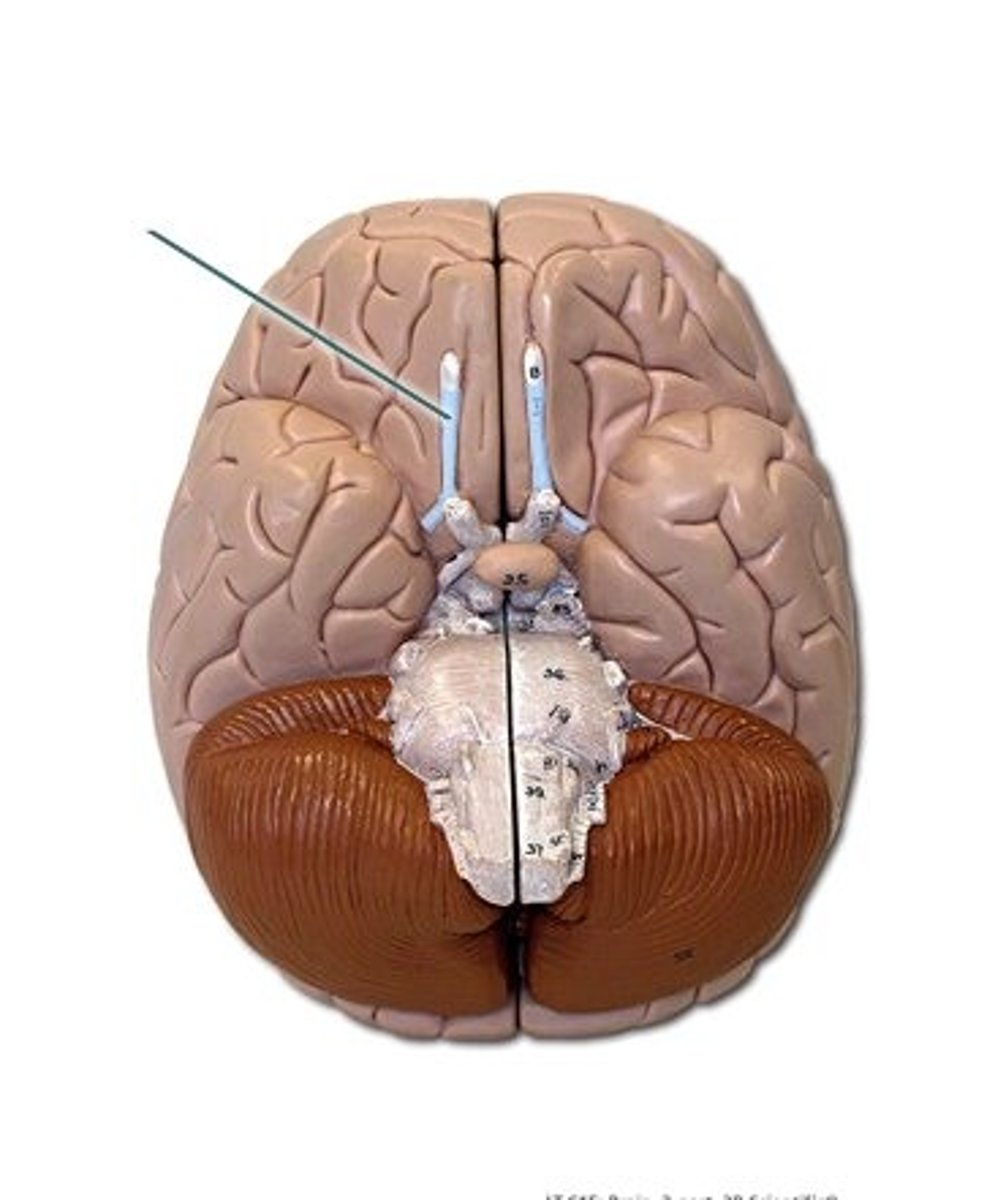

transverse fissure